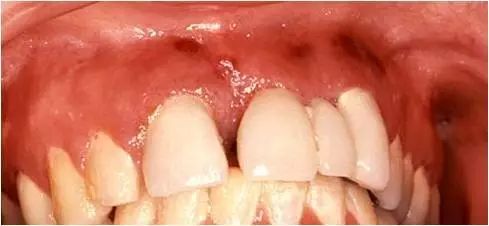

卡波济肉瘤

是一种罕见的血管恶性肿瘤,是艾滋病患者最常见的口腔肿瘤,常见于男性患者。好发于腭部和牙龈,呈单个或多个褐色、红色、蓝色或紫色的斑块或结节。